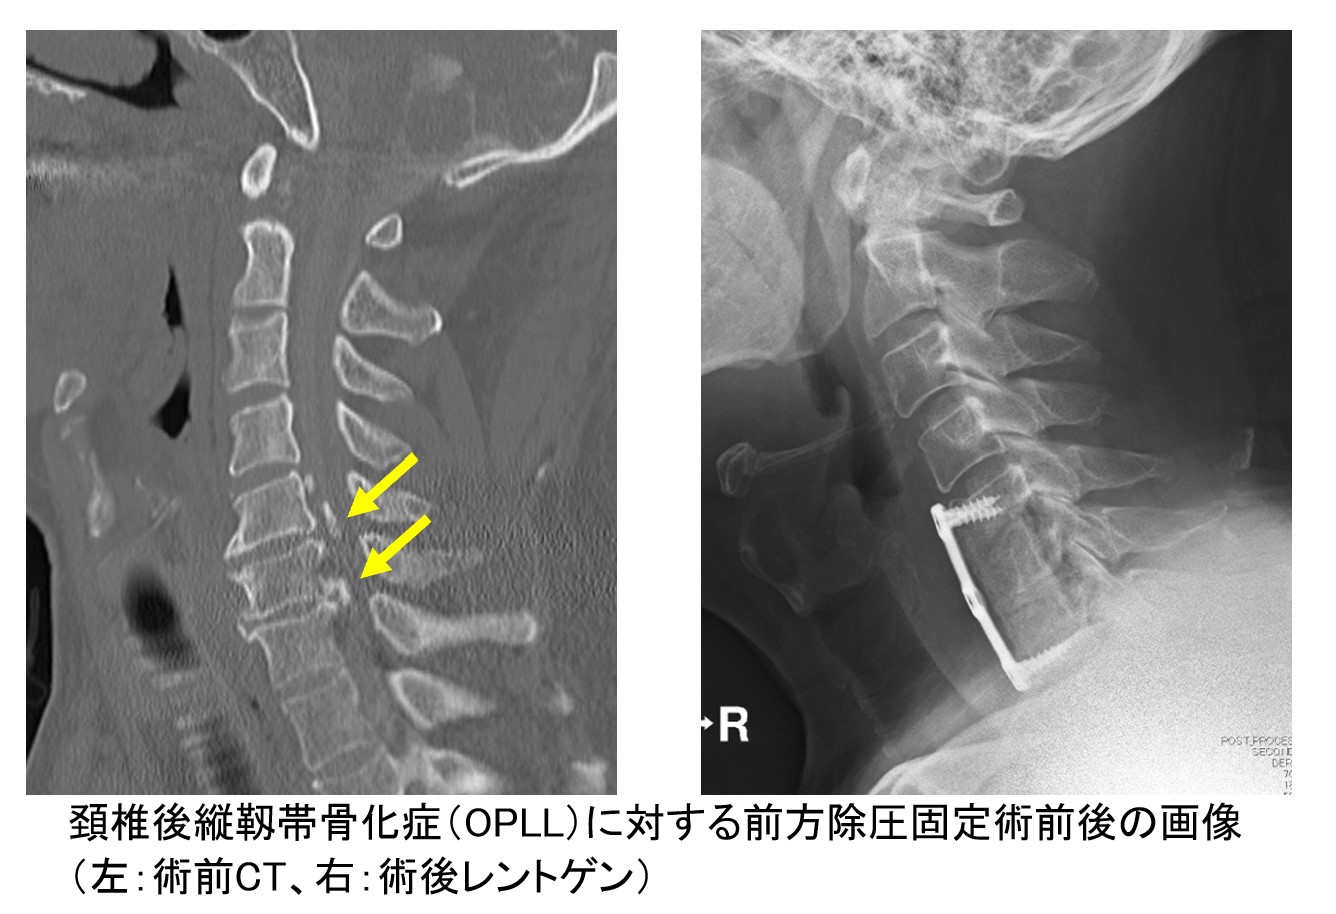

手術方法は骨化の大きさや部位などにより異なりますが、前方から骨化した靭帯を削り、ご自身の骨盤などの骨を移植して、インプラントで固定する『前方除圧固定術』、あるいは背骨の後ろからスクリューによる固定をした上で、椎弓(神経の後方の骨)や骨化した靱帯を削って脊柱管を広げる『後方除圧固定術』のいずれかを行うことが多いです。